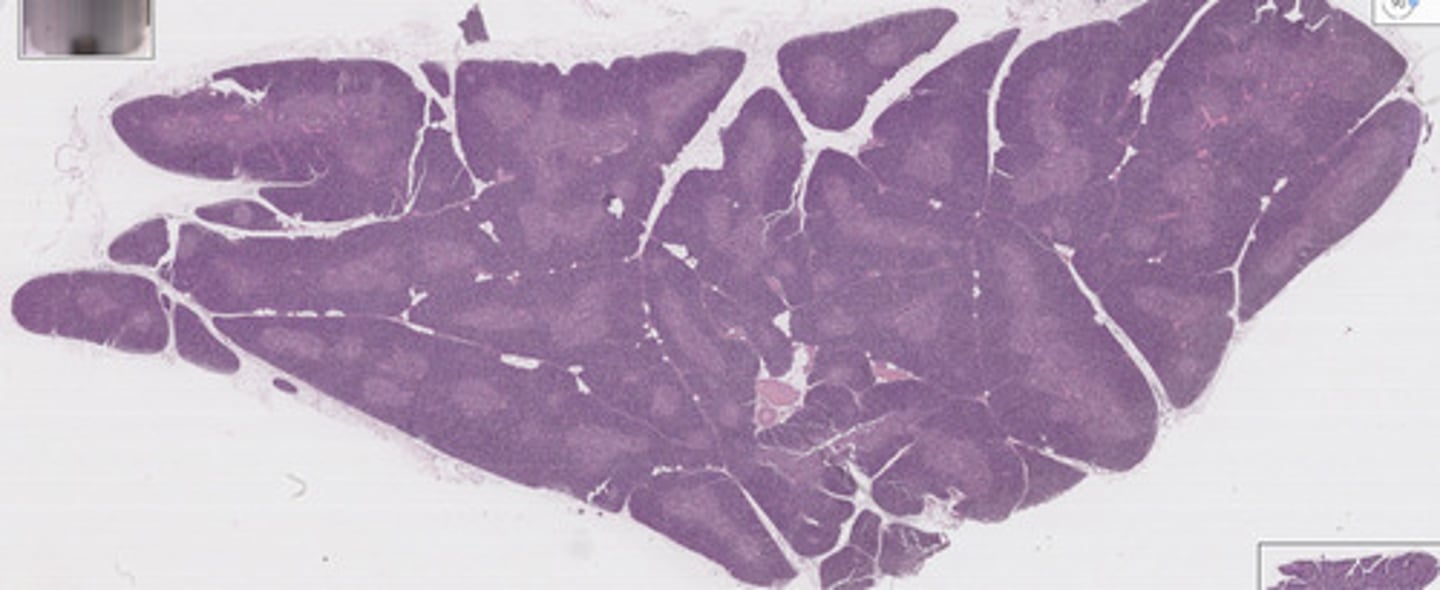

lymph node

what is this?

lymph node

what is this?